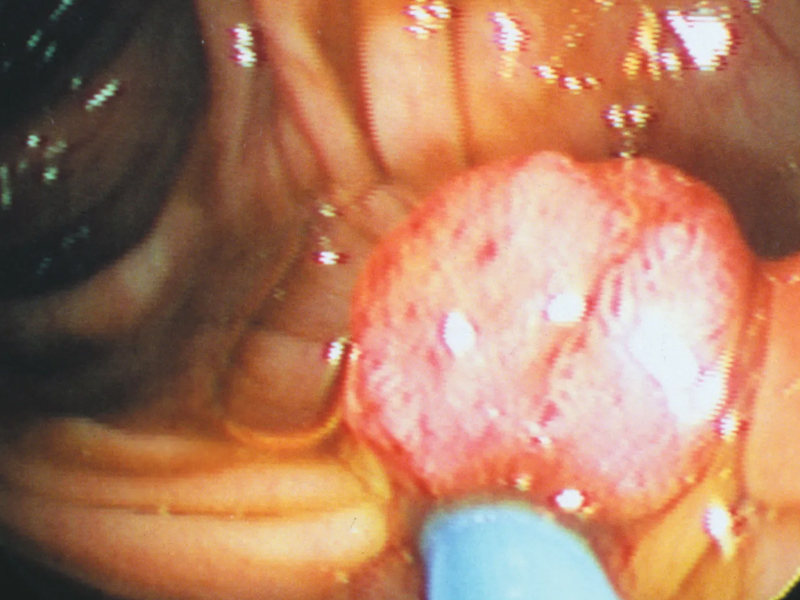

3、胃腸道息肉

有大約 15%~40% 的結腸癌源於結腸多發性息肉,其癌前期病程約為 5~20 年;腺瘤可以癌變,直徑小於 1cm 者癌變率低於 2%,直徑大於 3cm 癌變率超過40%。而如果是家族性腺瘤性息肉病(FAP)患者,25 歲時惡變率為 9.4%,30 歲為 50%,50 歲以前幾乎 100% 惡變,中位惡變年齡為 36 歲。